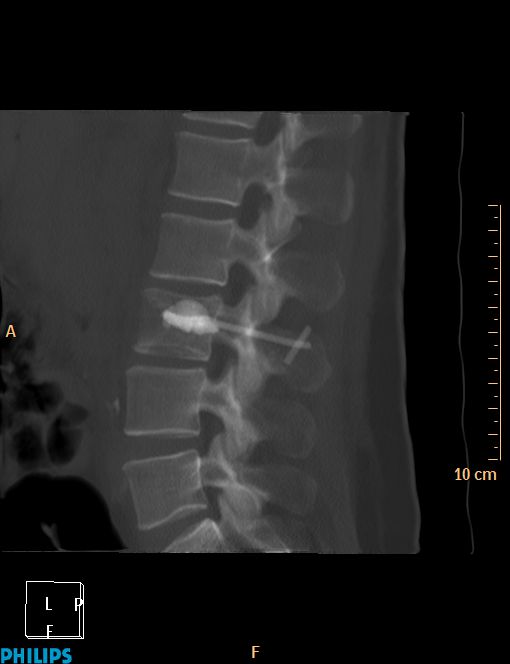

La vertébroplastie C'est ça d'attendre trop avant de retirer le trocard !!!